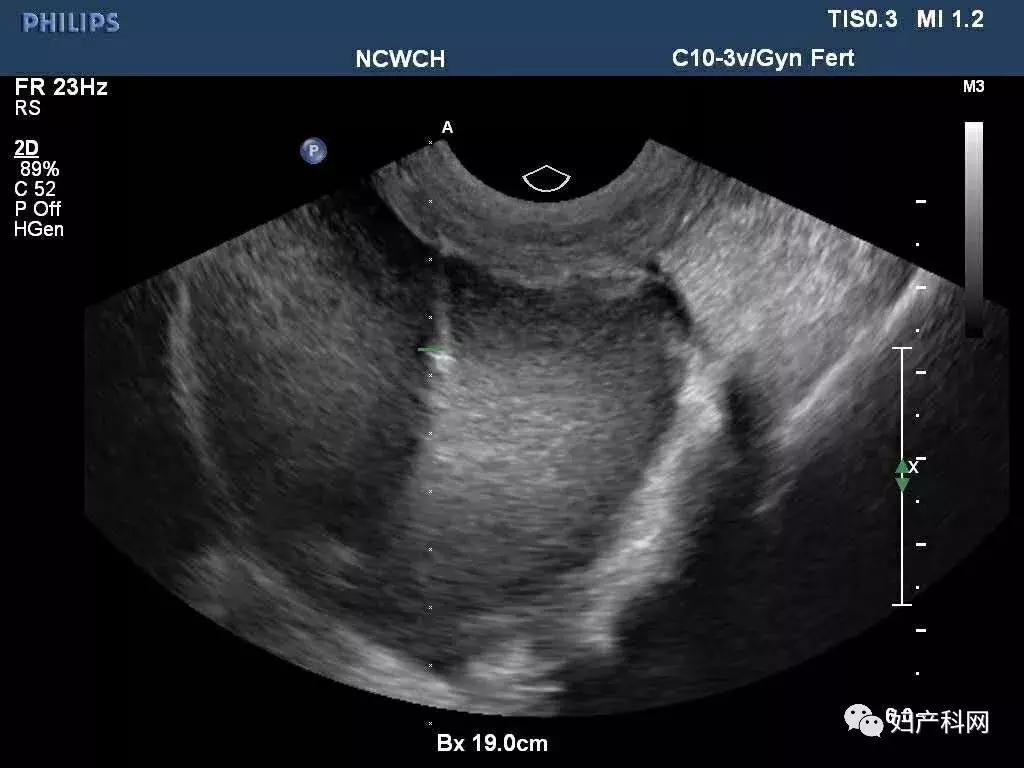

超声提示:右侧卵巢囊肿大小约7.4×4.7cm,巧囊不除外,ca125 37.7u/ml,HE4 40.6pmol/L。

术中超声

我们给这位患者选择的是经阴道卵巢囊肿穿刺+无水酒精固化,术中见右侧卵巢囊肿分为2房,分别从2房中抽出了约100ml巧克力样粘稠液体,共计200ml,每个房分别注入了50ml的无水酒精固化15分钟后抽出,术中同时放置了一枚曼月乐。

前几天这位患者再次来我们门诊复查,之前因为卵巢囊肿过大,超声甚至很难找到右侧正常卵巢组织,这一次可以轻松的发现了,囊肿也没有复发,当然后续还需要进行持续的随访。